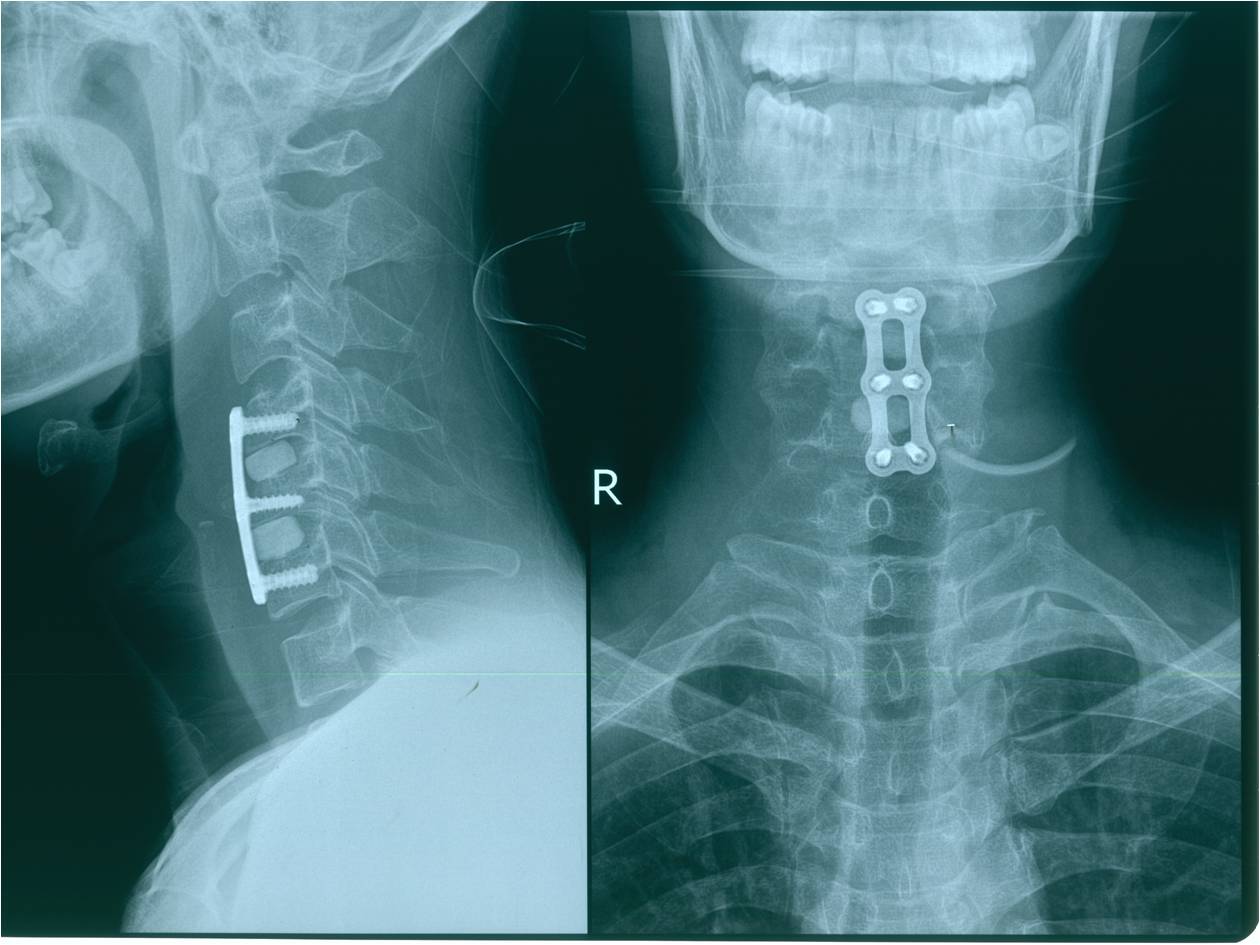

2012-11-18 车祸致四肢感觉、运动及二便功能障碍。

查体:意识清楚,呼吸均匀,查体合作。双侧感觉平面颈4,运动平面颈5. 颈6以下轻触觉保留至肛周,针刺觉消失。颈5以下只有肛门括约肌保留运动功能。下肢肌张力0级。腱反射消失。球海绵体反射可引出。当地医院行X片、CT、MRI检查